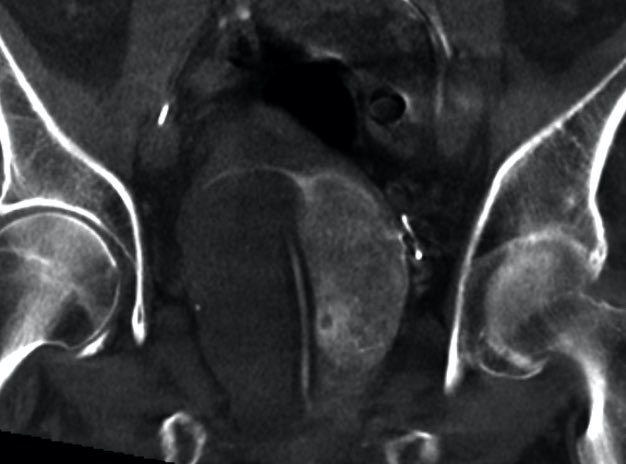

Great case!-the kind you will see at STREAM 2021–Sept 11-12 Washington DC thestreammeeting.com @SandeepBaglaMD @bonesz @SamMouli @TimMcClureMD @IR_Nutt @keithppereira @AriIsaacsonMD

Nice example of multiple feeders to large prostate: yellow-main prostatic artery, orange-distal int pudendal (pena cava), teal-retropublic branch of obturator, pink-distal sup vesical. (Colors courtesy of GE) @SIRRFS @SIR_ECS @StreamMeeting @UsaProstate